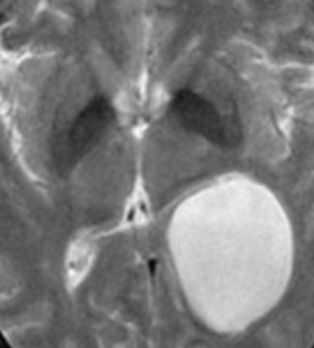

Порэнцефалические кисты - врождённые кисты различной этиологии, локализующиеся в паренхиме мозга или в области сосудистого сплетения желудочков.При МРТ головного мозга они обычно округлые, с гладкими стенками. Очень часто такие кисты сочетаются с аномалиями развития: отсутствием прозрачной перегородки и полимикрогирией. Содержимое порэнцефалической кисты при МРТ головного мозга ликворное, иногда с небольшой примесью белка.

Коллоидная киста - это врождённое нейроэпителиальное образование. Коллоидная киста выстлана эпителием и имеет фиброзную капсулу. Она составляют около 1-2% объемных внутричерепных образований. Обычно диагностируются в возрасте между 30 и 50 годами. Всегда расположена в переднее-верхнем отрезке III желудочка между отверстиями Монро. Контур ее четкий, форма округлая, содержимое бывает неоднородное. Размер от 3 мм до 4 см, при больших размерах она закрывает отверстия Монро и вызывает окклюзионную гидроцефалию. Сигнал зависти от примеси белка к ликвору. При наличии белкового мукоидного содержимого киста гиперинтенсивна на Т1-взвешенных МРТ головного мозга и гипоинтенсивна на Т2-взвешенных МРТ, но встречаются варианты гиперинтенсивные на МРТ головного мозга обоих типов взвешенности кольцевидные или смешанные. При МРТ головного мозга с контрастированием усиления сигнала не наблюдается.